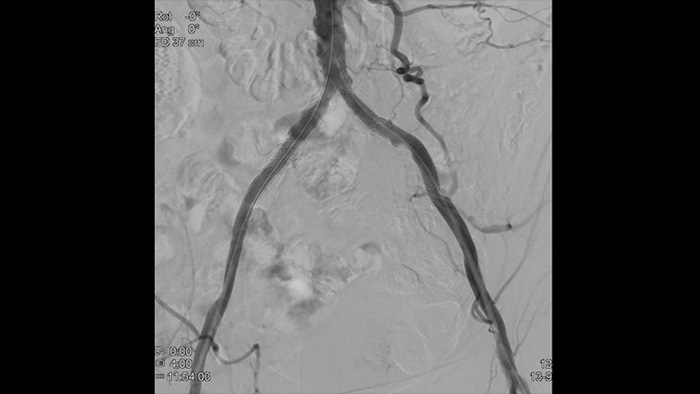

Unsere Bildgebungskatheter für periphere Blutgefäße erleichtern die Lokalisierung der Erkrankung und die Beurteilung der Läsionsmorphologie, einschließlich von Calcium und Thromben. IVUS kann Sie außerdem dabei unterstützen, die richtige Stent-Größe auszuwählen und die Vollständigkeit der Behandlung zu verifizieren.

Hochauflösende Bilder von Gefäßen mit hervorragender Detailgenauigkeit zur Unterstützung durchdachter Behandlungsstrategien, präziser Navigation und Verlaufsbeobachtung.